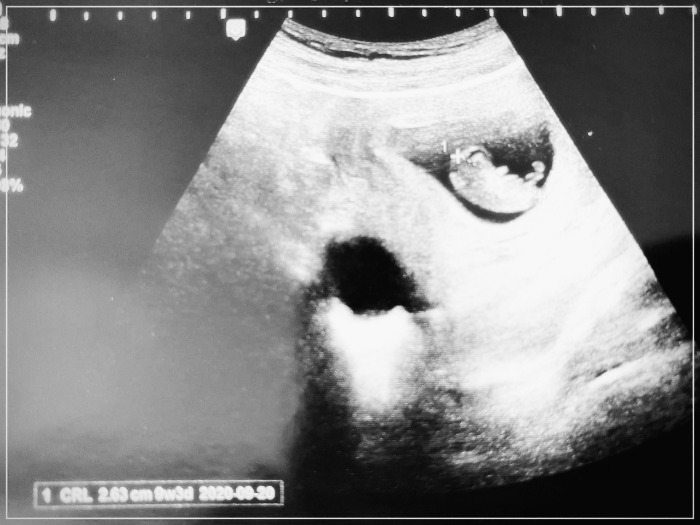

9주 차에 접어들면서, 입덧이 생기기 시작했어. 속도 울렁거리고 소화가 잘 안 되는 느낌이 계속되더라. 항상 딥슬립을 하던 나였는데, 자다가 3~4번씩은 화장실을 가야 했지. 그럼에도 불구하고 초음파를 통해 본 네가 아주 편안하게 둥실둥실 몸을 흔들면서 쉬는 모습을 볼 때마, 고생했던 기억은 전부 사라지더라.

아주 편안하게 둥실 거리던 9주 차 너의 모습